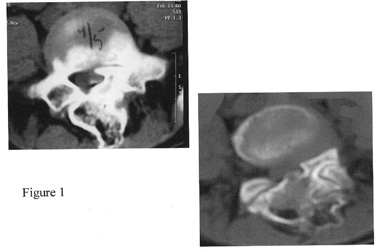

Spine The spine extends from the base of the skull to the tailbone. Spinal exostoses are rare (Figure 1). Spinal cord impingement is also a rare, but documented, complication of MHE. Cervical, thoracic or lumbar region can be affected. Scoliosis secondary to spinal osteochondromas and instability has been reported.

Affects of MHE on the Spine: more views of the spine can be seen on the MHE Research Foundation image gallery This section of the body is not commonly involved with MHE. Involvement of isolated vertebrae has been noted. Affects can range from instability to neural root or cord compression that can manifest as tingling, numbness or weakness in the involved roots or even major neurological deficits like paraparesis or quadriparesis in untreated cases. Rarely compression effects in the form of dysphagia, intestinal obstruction or urinary symptoms may occur.

Diagnostic Procedures: With any of the red flags mentioned earlier, the orthopedist will perform a thorough spinal and neurological evaluation. Plain x-rays of the spine and if required, advanced imaging may be performed. The presences and extent of the lesion are best delineated with CT, while MRI of the spinal cord demonstrates the area of spinal cord impingement. In rare cases of peripheral nerve compression electromyography may be performed to check status of the nerve.